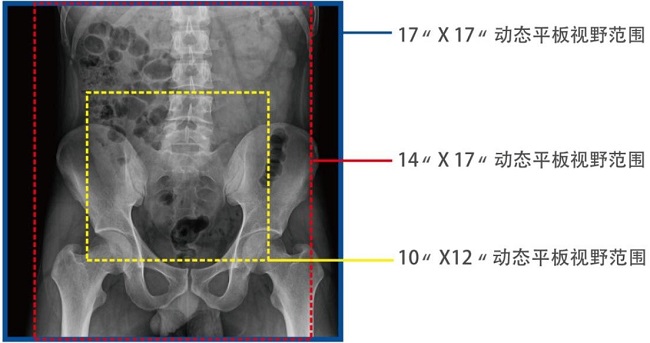

17*17英寸的超高清像素動態(tài)平板探測器,更大的視野范圍,能對胸部腹部等部位實(shí)現(xiàn)大范圍全覆蓋,動靜態(tài)之間無感切換。透視檢查無須對患者重新定位便可觀察到足夠大的人體器官組織,避免漏診誤診。

大尺寸動態(tài)平板技術(shù),覆蓋檢查面積范圍廣,輕松實(shí)現(xiàn)胃十二指腸等大面積造影,無需移動即可觀看整個動態(tài)過程,避免噪點(diǎn)對圖像的影響。